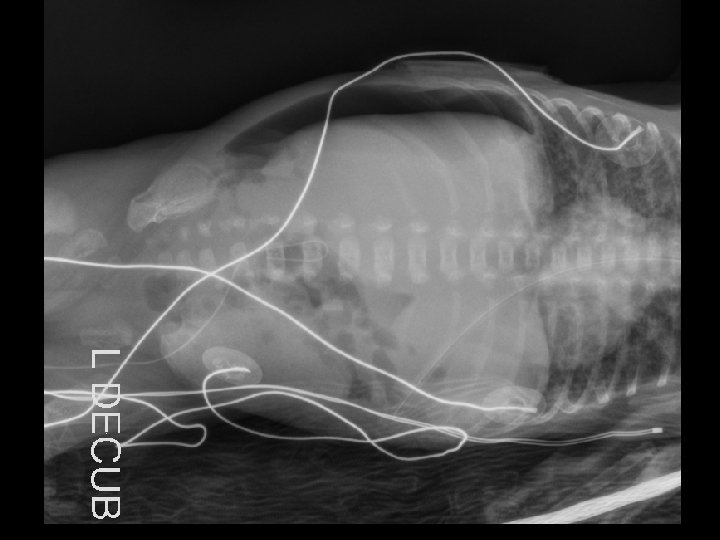

Case 1 Day 12 • On day 12 an Xray was done……

Case 1 Oh, oh…. . • On day 12…. – Free air noted on abdominal XR – No clinical abdominal symptoms • Rx…. – Intubated for transport – NPO – Antibiotic coverage expanded – Transported to Oakland Anna Bergquist CHO MR 960776